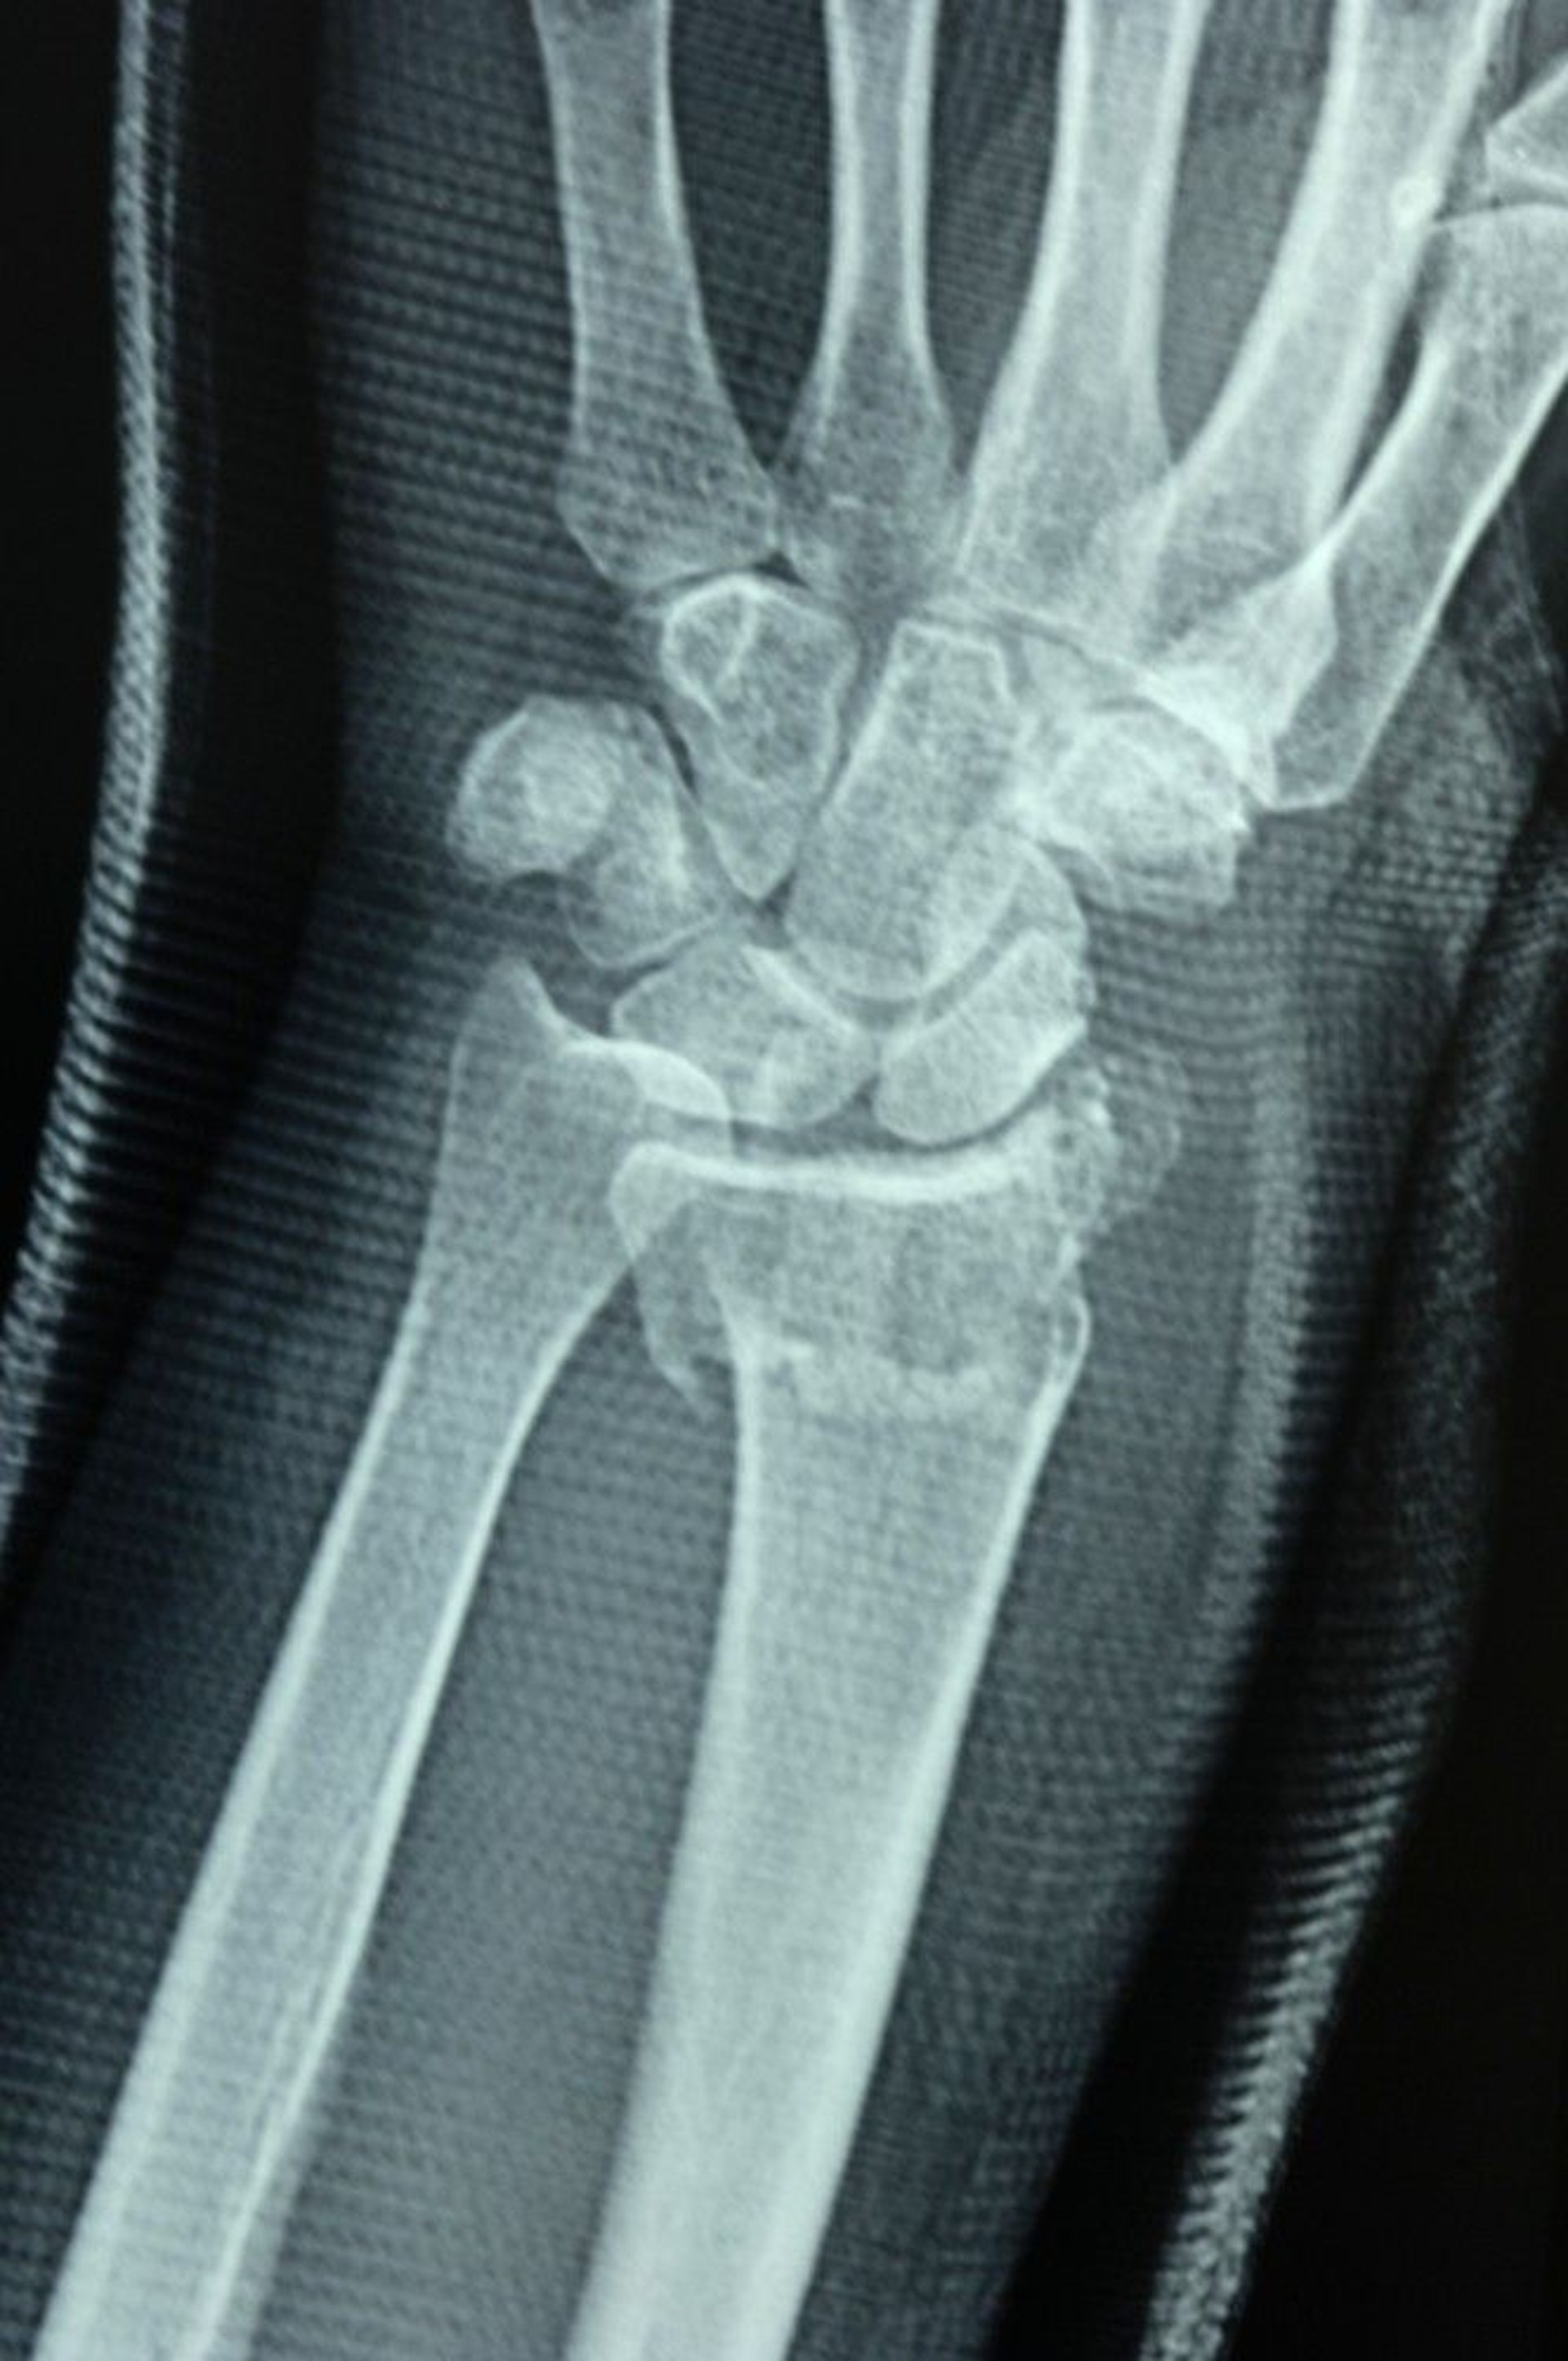

Distal Radius Fracture

The radioulnar joint is disrupted, as shown by the failure of the joint surfaces of the distal radius and distal ulna to align, causing a step-off.

DR P. MARAZZI/SCIENCE PHOTO LIBRARY